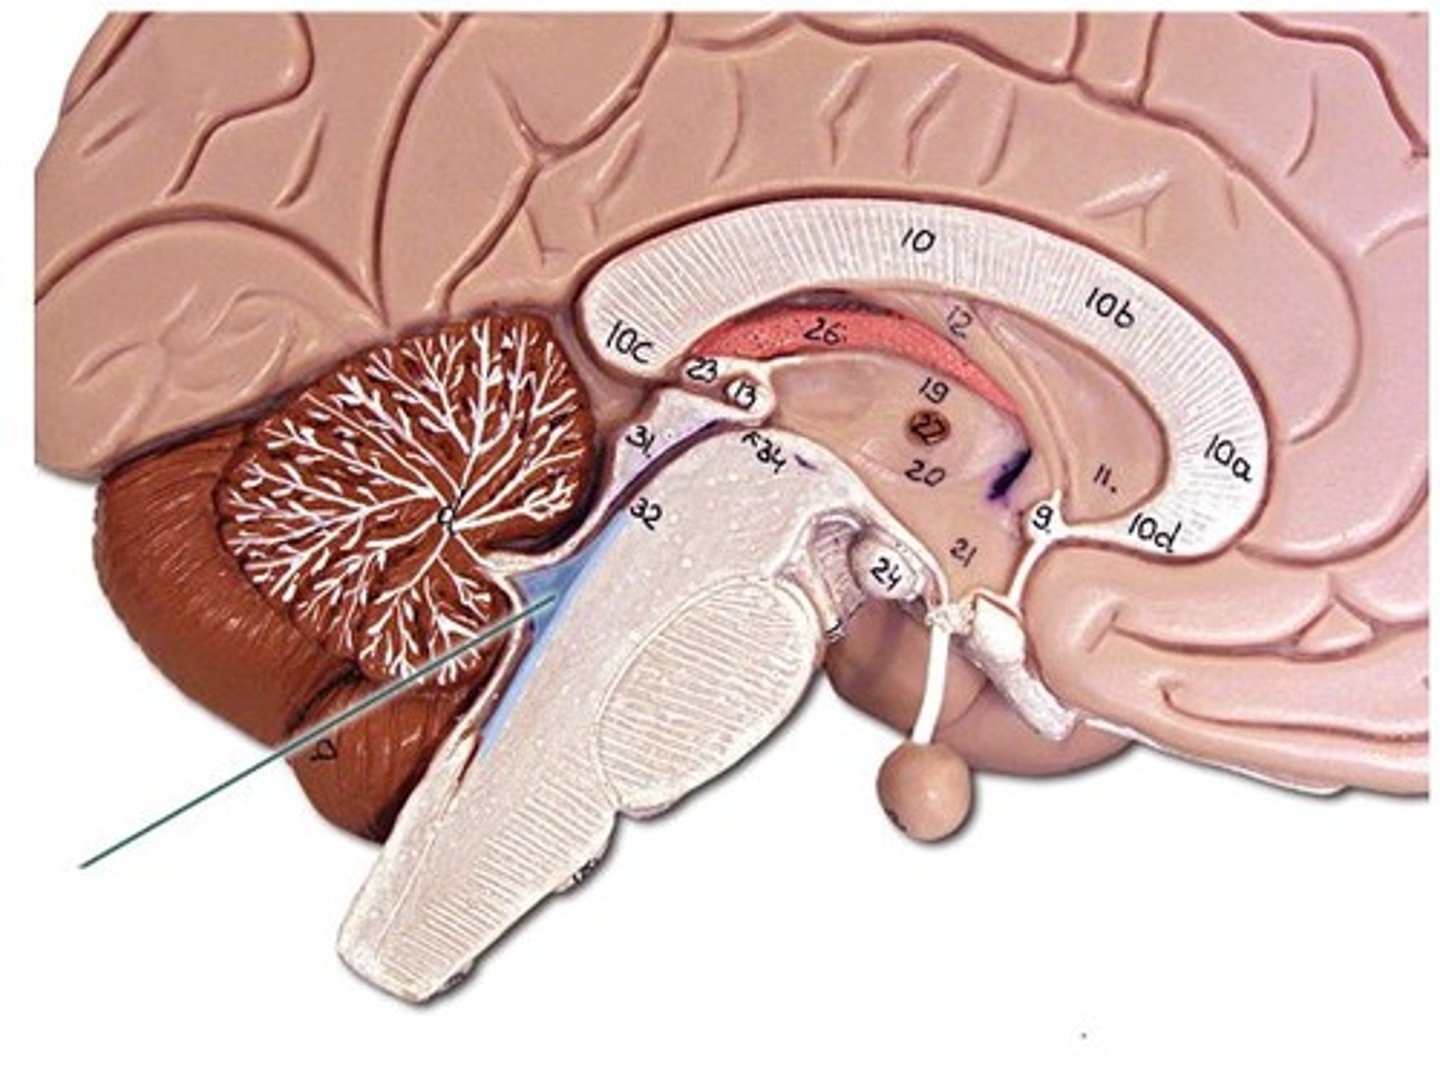

Diencephalon

Sits on top of the brain stem,

Enclosed by the cerebral hemispheres,

Made up of 3 parts: the Thalamus, Hypothalamus, and Epithalamus

Thalamus

Bilateral egg-shaped nuclei, which forms superolateral walls 3rd ventricle,

Relay station for information coming into cerebral cortex:

-Will sort and edit the info

-Also provides a crude recognition of sensation as pleasant or unpleasant before it sends info on to cortex where specific stimulus localization and discrimination still occur

Hypothalamus

Located under thalamus where it caps the brain stem and forms inferolateral walls of 3rd ventricle,

Main visceral (involuntary) control center of body is vitally important to overall body homeostasis (few tissues in body escape its influence),

hypothalamus chief homeostasis controls

1) Important autonomic (ANS) control center,

2) Center for emotional response (limbic system),

3)Regulates Body tempt., food intake, water balance and thirst, and sleep-wake cycle

4) Control of endocrine system functioning: pituitary gland

Pituitary gland

Is attached to the hypothalamus and the hypothalamus is therefore indirectly influences many body functions by sending signals through to regulate its secretion of hormones

Epithalamus

Forms the roof of the 3rd ventricle,

Houses the pineal gland or body (an endocrine gland) (Melatonin production: sleep/wake cycle),

Includes the choroid plexus (forms cerebrospinal fluid- CSF)

Choroid Plexus

Forms Cerebrospinal Fluid

Choroid Plexus

Pineal Gland

Melatonin Production (sleep/wake cycle)

4th Ventricle

Cerebrospinal Fluid (CSF)

1) Formed by choroid plexus in each ventricle.

2) Similar to blood but no red blood cells and much lower protein level.

3) Supplies nutrients and forms protective fluid cushion that gives buoyancy to CNS structures:

-Reduces brain weight by ~97% and prevents it from crushing under its own weight (very delicate)

4) Circulated in subarachnoid space, ventricles, and central canal (facilitated by ependymal cells that line each of these areas)

Ventricles

1) Right & left lateral ventricles:

-Anterior, Posterior & inferior horns

2) 3rd Ventricle, Cerebral aqueduct, 4th ventricles

4) Apertures (Narrow openings) into subarachnoid space of spinal cord